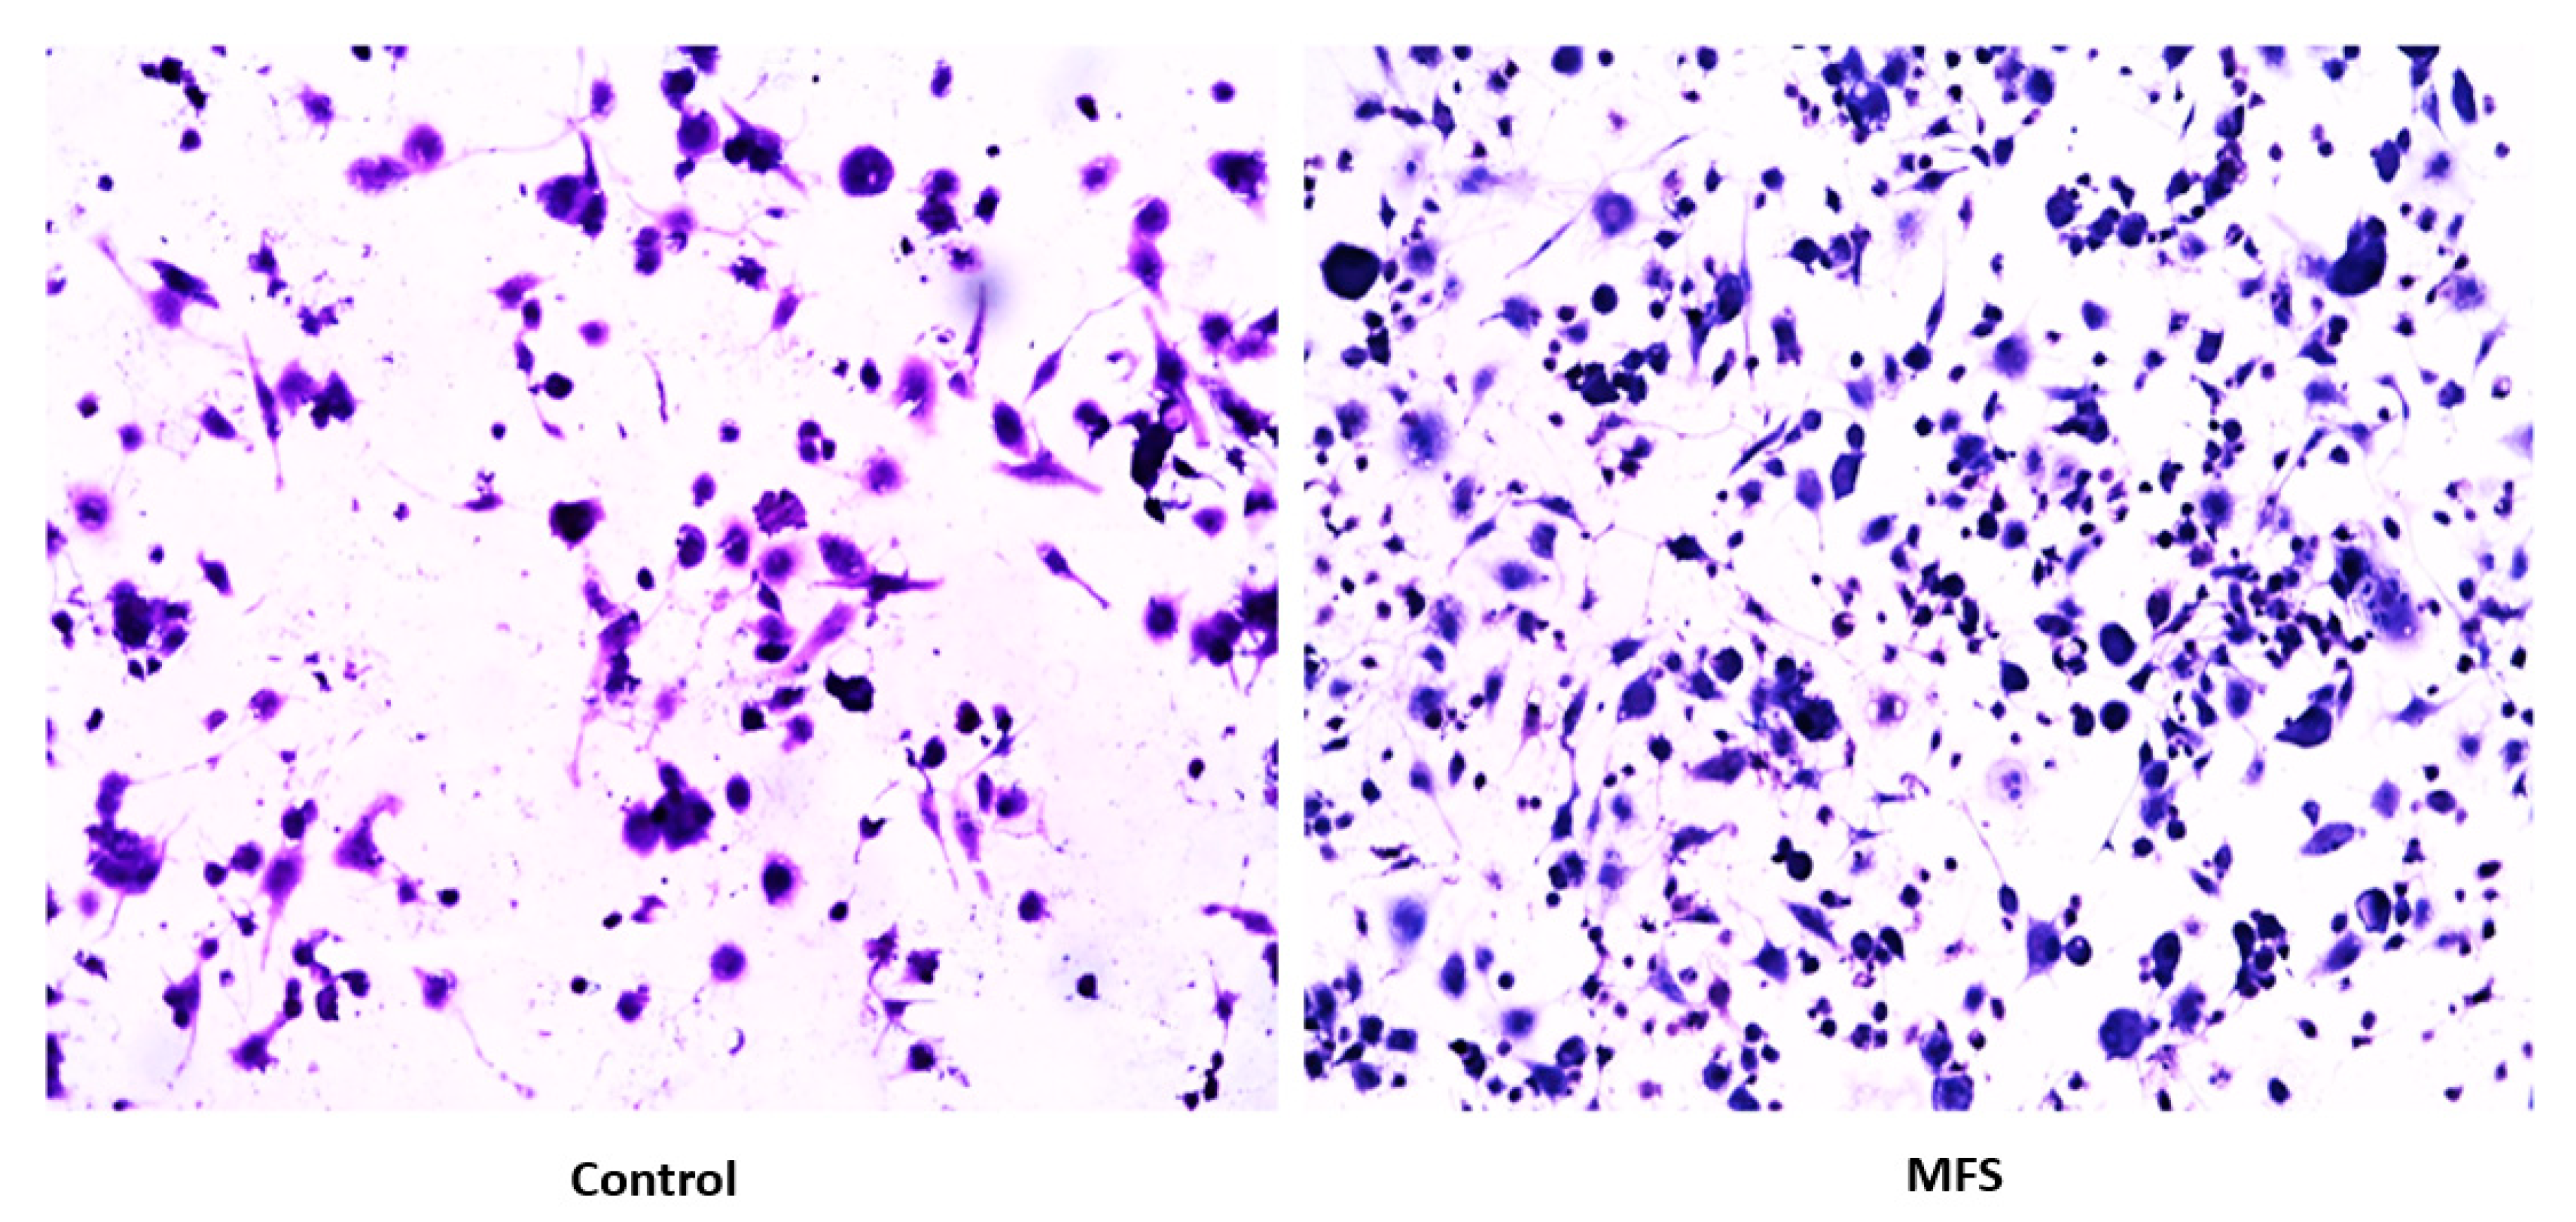

2.10. Hematoxylin and Eosin Staining of Human Granulomas from Individuals with T2DM

H&E staining of Mtb infected granulomas from individuals with T2DM showed an increase in cell density and aggregation with MFS versus sham treatment after 15 days (Figure 12).

Lastly, we tested the influence of MFS treatment on PBMCs collected from individuals with T2DM, a patient population that is significantly more susceptible to Mtb infections [1]. Consistent with findings from the healthy individuals, PBMCs of T2DM patients treated with MFS exhibited more robust cellular aggregations and granuloma formation (Figure 12). Correspondingly, after MFS administration the PBMC bacterial burden was reduced to roughly one-third that of the T2DM infected control (Figure 13). Although the abundance of Mtb was significantly diminished with MFS treatment, the quantity of bacteria remaining was still over double that of levels linked to the same experiments in healthy study participants (Figure 14). This demonstrates that while MFS supplementation reduced Mtb infectivity in both healthy individuals and those with T2DM, it is not sufficient to cause complete Mtb elimination.

Figure 12. Hematoxylin and Eosin staining of untreated and MFS-treated human granulomas from individuals with T2DM. Microscopy work was done with a light microscope at 100× magnification under oil immersion.